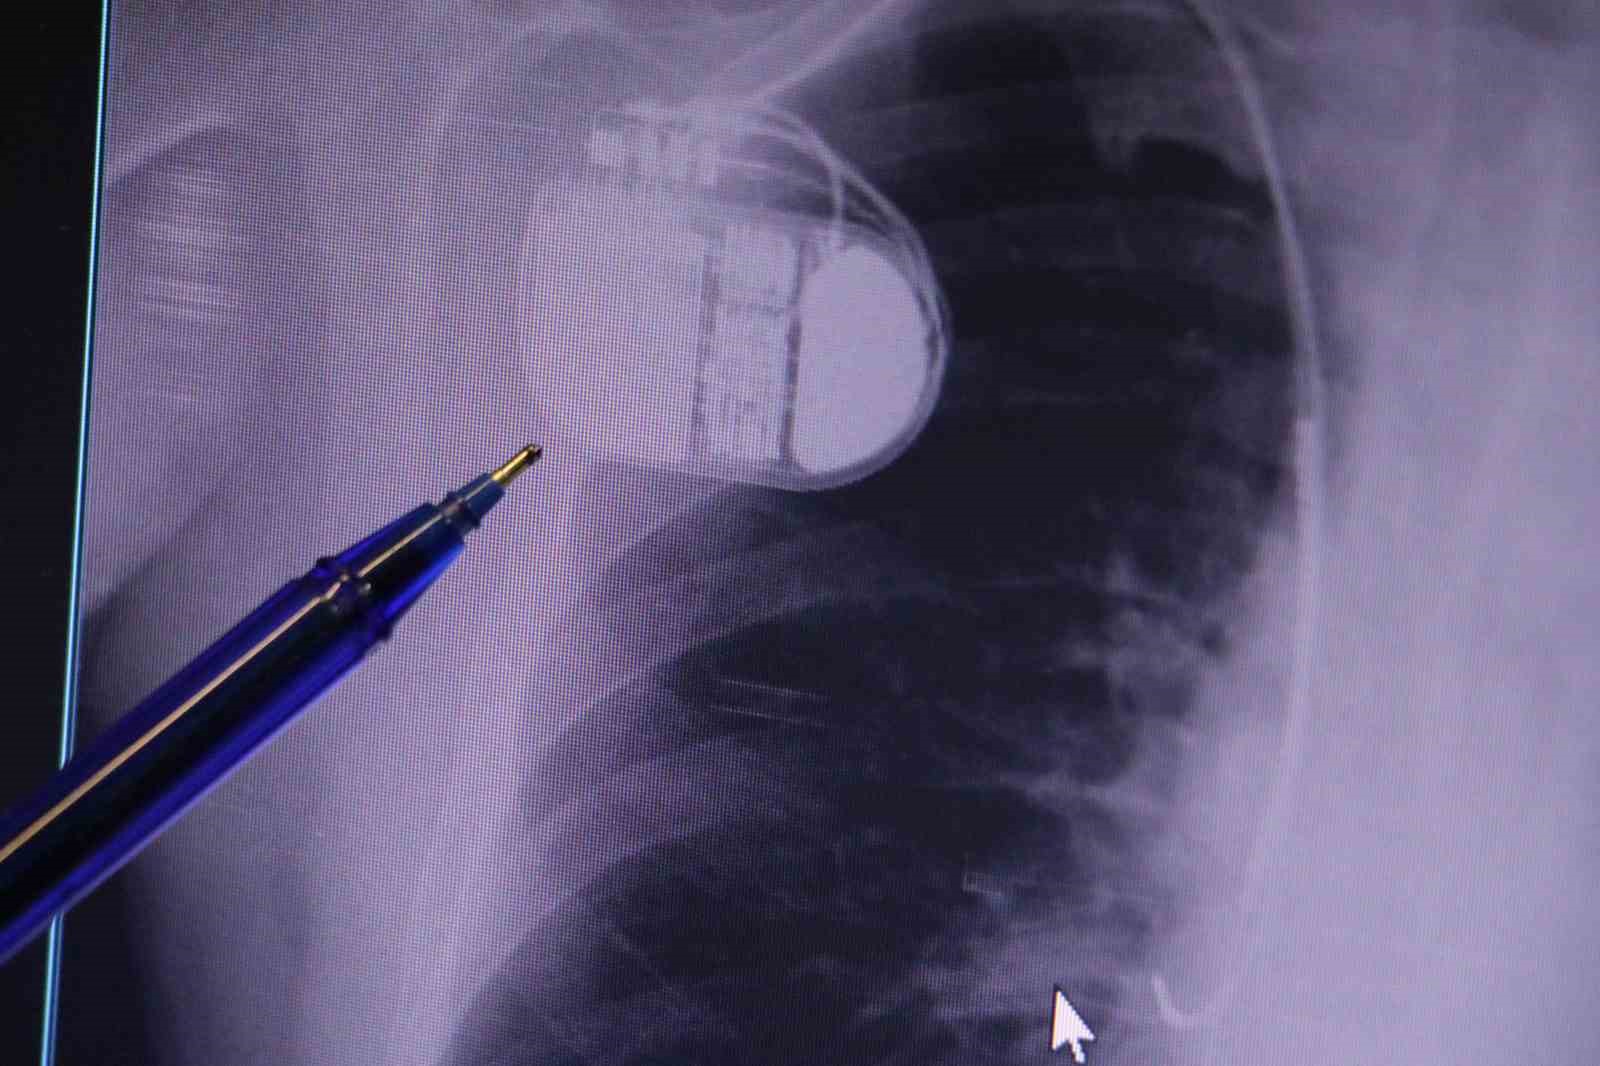

Kalp krizleri sonrası kalp dokusunun zarar gördüğünü söyleyen İsmail Erdoğu, "Dünyada artık kalp hastalıkları en sık ölüm sebeplerinden biri. Kalp hastalıklarında çok fazla grup var. Biz kalp hastalıkları deyince sadece kalbinde stent olan ve damarlarında sorun bulunan insanlardan bahsetmiyoruz. Aynı zamanda tansiyon ve şeker hastaları da kalp hastalıklarına aday. Toplumun yaklaşık yüzde 30-35’lik bir kısmını kapsıyoruz. Çok yaygın bir hastalık ve bu hastalıkta teknolojik kapsamda, ilaç konusunda son 30 yılda çok ciddi gelişmeler oldu. Geçmişte insanları hastanelerde kalp krizinden dolayı kaybederken şimdi hastaneye başvurular sonrasında yaşama tutunmak büyük oranda mümkün. Yaşanan ölümler ise genellikle hastaneye gelmeden önce gerçekleşmekte. Kalp krizinden kurtulmanın hastalarda belli bir bedeli oluyor. Kalp krizi sonrası kalpteki dokular zarar görüyor ve kalp yetersizliği oluşuyor. Bu kalp yetersizliği olan kalplerde ritim bozuklukları ve ani ölümler gibi sorunlar gündeme gelebiliyor. Bunlardan uzun vadede korunmak için hastalarda mutlaka bir kalp piline ihtiyaç duyuluyor" dedi.

Kalp pilleri ile MR cihazına girilebileceğini belirten Erdoğu, "Çok büyük bir ameliyat değil ama yine de ciddi bir cerrahi işlem. Kalp pili, tıpta son 30 yılda yaşanan gelişmelerden en büyüğü. Bir bilgisayarın küçültülüp insan vücuduna konulmuş hali aslında. İnsan ömrünü ciddi oranda uzatan bir tedavi. İnsanlar bir şokla hayata tutunurken, pil olmasaydı öleceğini düşündüğümüz birçok hastamız var. Kalp pilinin bu özelliği, uygun hastalarda ciddi oranda ani ölümü engelliyor. Hastanın başına gelecek bir kalp durması durumunda yanında bir sağlıkçı yoksa, onun ritmini düzeltecek defibrilatör cihazı yoksa hastayı hayatta tutmak mümkün değil. Uygun endikasyonlarda kalp pili olduğu zaman, pil hastaların ritmini algılıyor ve acilde yapılan şoklamayı yaparak hastayı hayata döndürüyor. Kalp pillerinde yeni teknolojilerle MR’a girmek mümkün, tomografiye zaten girebiliyorlar. Tarama cihazlarından geçmelerini uygun görmüyoruz. Bu tarz durumlarda hastalarımız ’kalp pilim var’ dediğinde muaf tutuluyorlar. Kalp pilleri ciddi teknolojik cihazlardır. Vücudun içindeki titreşimi, örneğin mikser kullanmak, kolunu sallayacak herhangi bir eylem kalp pilinde olumsuz etki oluşturabilir. Soğuk havalarda vücutta oluşan ciddi titremeler kalp pilinin hafızasını karıştırıp kalbin durduğunu düşündürebilir ve gereksiz şoklama yapabilir. Bu tarz kişilerin soğuk havalarda daha temkinli olması gerekir" diye konuştu.